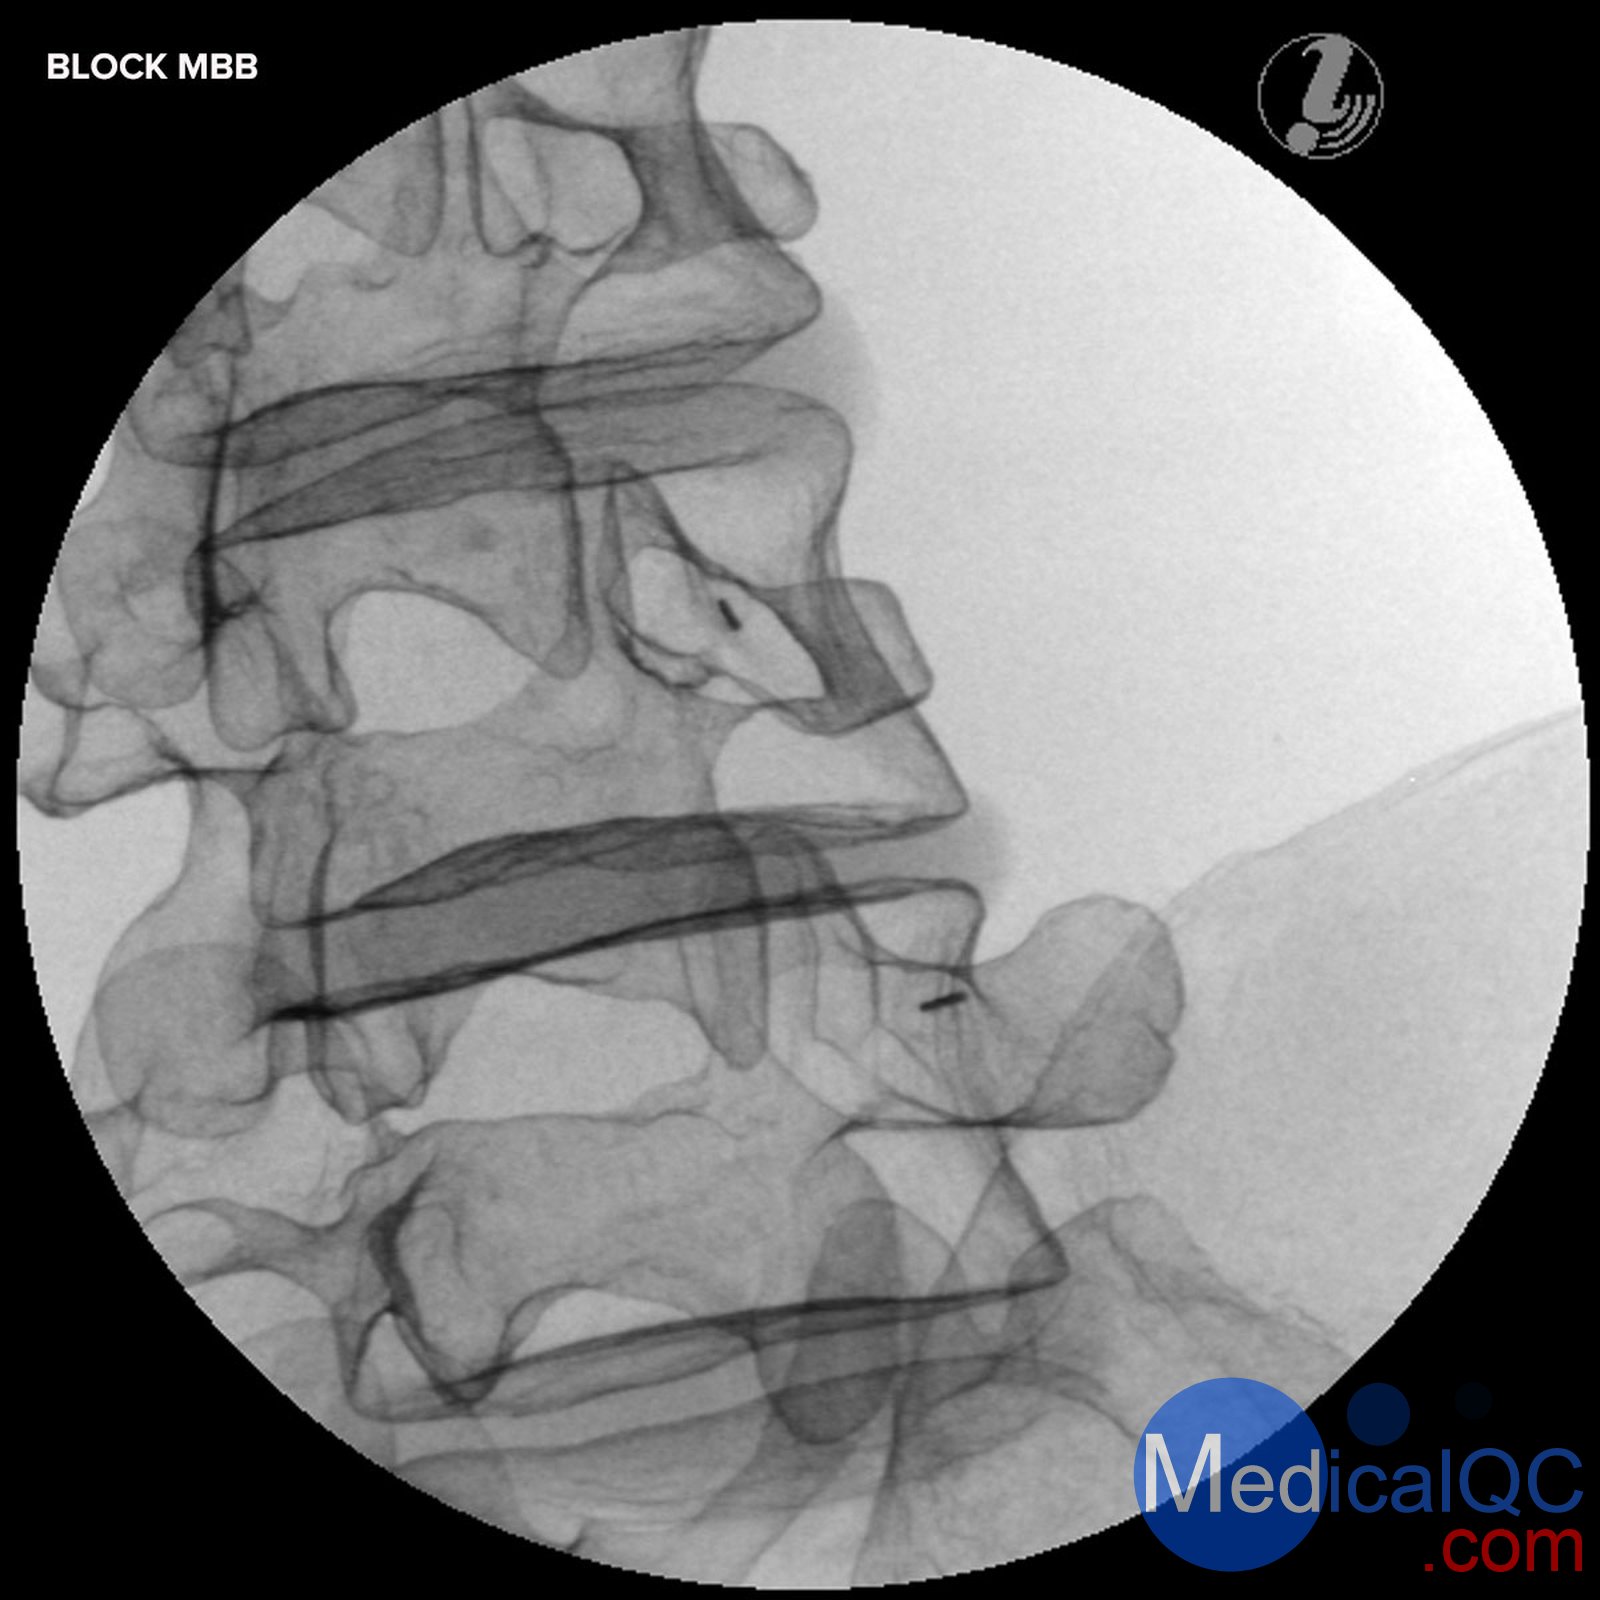

封鎖中位數分支(MBB / RF)

Image Guided Lumbar Spinal Injection Trainer

Improve outcomes of spine interventions with standardized image guided injection training

The Image Guided Lumbar Spinal Injection Trainer enables trainees to develop a three-dimensional understanding of the procedures for successful spine interventions. They will learn to correlate imaging with the lumbar spinal anatomy relevant to interventional pain procedures, to identify the target tissue and vulnerable structures using imaging and anatomic inspection, and to apply best practices to ensure patient safety during the interventional spine procedures.

Using the Spinal Injection Trainer is an economic alternative for imaging techniques courses on cadavers and offers the instructors a reliable, standardized patient simulation always ready to use:

Life-like radiopacity for realistic x-Ray images

Realistic injection haptics

Anatomically accurate bone structure

Visually identifiable landmarks

The following image guided spinal interventions can be trained on the simulator:

Medial Branch Block (MBB/RF)